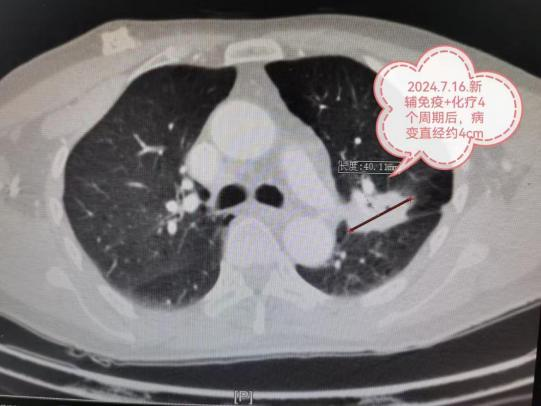

4月16日,贵州航天医院第57次晨读会由我院心胸外科副主任医师罗明洋作学术交流,他以“常见膈疝的诊治”为题,从膈疝的基本概念切入,系统讲解了食管裂孔疝、胸骨旁裂孔疝、胸腹裂孔疝及膈膨升的临床表现与诊疗方案,重点分享了如何修复食管裂孔及补片的使用与如何恢复胃食管阀瓣、食管下段括约肌及his角等核心技术。并通过典型病例详细阐述了腔镜微创食管裂孔疝修补术和胸腔镜下膈肌折叠缝合术的操作要点。 心胸外科专家简介 陈光春 心胸外科主任、学科带头人,副主任医师 曾工作于陆军军医大学附属大坪医院等军队大型综合性三甲医院及全军唯一胸外科研究所。 临床擅长:从事胸外科临床工作20余年,对食管癌、食管裂孔疝、反流性食管炎、肺结节、肺肿块、肺癌、血气胸、脓胸、纵隔肿瘤、胸腺瘤、重症肌无力、手汗症、胸部外伤等疾病的外科诊疗有丰富的临床经验。擅长电视胸腔镜肺癌根治术、食管癌根治术、纵膈肿瘤切除术等大型胸外科微创手术,特别擅长单孔胸腔镜微创手术,熟练掌握3D-技术引导下单孔胸腔镜肺段、亚段、联合亚段切除术、剑突下单孔胸腔镜纵膈肿瘤切除术等胸外科微创技术;设计并开展西南地区首例经左胸单孔辅助腹腔镜胃食管交界部癌微创手术。 中国医师协会手汗症专委会全国委员,吴阶平医学基金会交感神经外科专委会全国委员,重庆市中西医结合学会胸外科专委会常务委员,重庆市医学会微创专委会胸外科学组委员,重庆市医药生物技术协会肺癌防治专委会委员,重庆市医药生物技术协会食管癌防治专委会委员。 曾荣获重庆医科大学“受学生好评教师”称号和讲课比赛三等奖。发表学术论文10余篇,手汗症微创手术治疗有较大影响力,成功吸引全国各地300余名患者慕名前来就诊,2016年当选为中国医师协会胸外科分会手汗症全国专家组首批25位委员之一。 罗明洋 中共党员,心胸外科副主任医师 临床擅长:从事胸外科工作近20年,对胸部外伤、胸壁重建、气胸、脓胸、包裹性胸腔积液、肺结节、肺肿块、肺癌、食管癌、纵隔肿瘤等胸外科疾病的诊治具有丰富的临床经验,特别擅长肺癌、食管癌、纵隔肿瘤的电视胸腔镜微创手术。 心胸外科简介 心胸外科现有副主任医师2名,医学硕士4名。科室团队擅长电视胸腔镜肺癌根治术、电视胸腔镜食管癌根治术、电视胸腔镜纵膈肿瘤切除术等大型胸外科微创手术,设计并开展了西南地区首例经左胸单孔辅助腹腔镜胃食管交界部癌微创手术;手汗症微创手术治疗在全国有较大影响力,是中国医师协会手汗症专委会全国委员级别单位,吴阶平医学基金会交感神经外科专委会全国委员级别单位,已为全国10余个省、直辖市、自治区患者成功进行手术。并在食管癌、食管裂孔疝、反流性食管炎、肺结节、肺肿块、肺癌、血气胸、脓胸、纵隔肿瘤、胸腺瘤、重症肌无力、手汗症、胸部外伤等胸外科疾病的诊疗方面有着丰富的临床经验。 专科特色 (一)单孔胸腔镜技术 相比传统开胸手术以及很多医院的3孔或4孔胸腔镜手术,我院心胸外科仅行1个孔的单孔胸腔镜手术,创伤更小、疼痛更轻。 传统开胸切口 4孔胸腔镜 3孔胸腔镜 3cm单孔胸腔镜 (二)3D技术引导下亚肺叶精准微创切除术 3D技术在医学的应用,使精准医学变为可能。如图:右上肺9个结节,3D技术引导下,单孔胸腔镜RS2段切除+流域法RS1bi+RS3bi联合亚亚段切除,将9个肺结节一网打尽。如果没有3D技术指引,该患者只能被迫切除整个右肺上叶,而在3D技术指引下仅切除右肺上叶1/3左右。 (三)新辅助治疗后的肺癌微创根治术 偏晚期的肺癌手术机会渺茫,新辅助治疗(术前免疫、靶向、化疗等)可让患者重获根治性手术机会。如图:7.7cm左上肺癌,若直接手术,可能无法切除或被迫切除左全肺。新辅助免疫+化疗4个疗程后,病变由7.7cm缩小到4cm,在单孔胸腔镜下肺动脉成形完成左上肺癌根治术(左上肺叶切除+淋巴结清扫),不仅只切除了左上肺保留住了左下肺,而且术后病理检查显示术前用药后残存癌细胞比例仅残存6%,也就是说4cm肿块里面94%的组织已经没有癌细胞,远期疗效更佳。 (四)新辅助治疗后的胸腔镜微创食管癌、贲门癌根治术 与肺癌类似,偏晚期的食管及贲门癌手术机会渺茫,因为有了新辅助治疗(术前免疫、靶向、化疗等)而重获根治性手术机会。如图:中段食管癌,病变与周围血管等关系紧密,直接手术估计很难完整切除。3个疗程新辅助免疫+化疗后病变明显缩小,行颈胸腹切口胸腹腔镜联合微创手术后治愈。 (五)经剑突下胸腔镜前纵隔肿瘤切除术 前纵隔肿瘤传统手术需全胸骨劈开,创伤大且疼痛剧烈。我科多采用剑突下胸腔镜手术,创伤小,疼痛轻微。如图:26岁女性,前上纵隔畸胎瘤,最大直径约7CM,与周围大血管关系紧密,经剑突下单孔胸腔镜手术成功切除。 传统全胸骨劈开, 恐怖! 剑突下(“心窝子”)约4cm单孔胸腔镜 (六)手汗症微创手术 作为中国医师协会手汗症专委会全国委员级单位,参与全国手汗症诊疗技术优化及质量控制专家共识编写,手汗症微创手术治疗在全国有一定影响力,吸引全国各地患者慕名来院手术。 诊疗范围 主要开展胸部相关疾病的外科手术治疗及相关恶性肿瘤的全程治疗及管理(新辅助治疗、手术、辅助治疗等)。 end